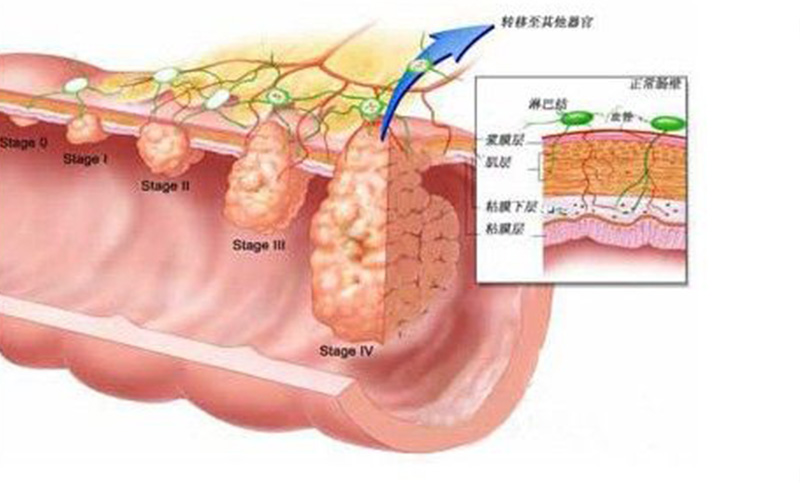

直腸息肉細胞

直腸息肉惡變細胞

A:直腸息肉是指直腸內粘膜腸腔內的突出隆起性的病變,一般可分為炎症性,增生性或者是腺瘤性息肉三種,增生性息肉或者炎症性息肉可能與感染因素或者是損傷因素有關係,而腺瘤性息肉可能與環境因素和遺傳因素有關,能夠發生癌變。炎症性和增生性息肉不會發生癌變……